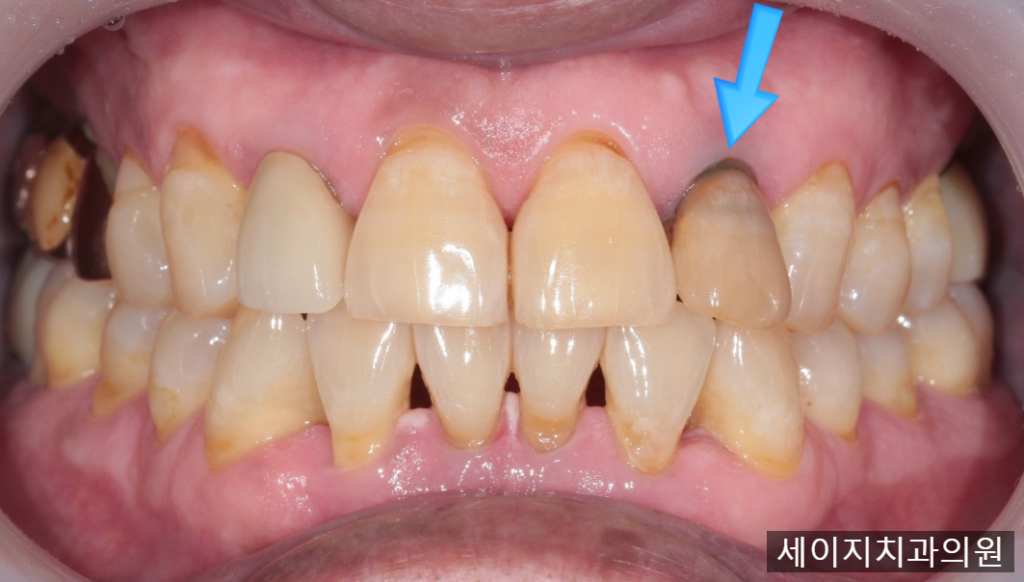

앞니가 흔들거리고 곧 빠질 것 같아요.

오늘 소개해드릴 케이스의 경우, 대합치아와의 교합 간섭으로 인해 교합외상이 발생되어 있었으며, 이로 인해 치아의 심한 동요도를 보였습니다.

먼저 x-ray와 CT를 이용하여 정확한 뼈의 모습과 치아의 상태를 관찰하였습니다.

CT상으로는 입술에서 가까운 잇몸뼈의 흡수가 관찰되었습니다.

환자분께서는 신경치료를 받은 치아이기에 심한 통증은 나타내진 않으셨지만 치아가 계속 흔들거려서 빠질것 같다고 표현해 주셨습니다.

잇몸뼈의 소실이 크기에, 임플란트 진행시 심미적인 요소를 맞추기가 어려워 보였습니다. 때문에 환자분께 브릿지 치료도 하나의 옵션으로 권유드렸으나, 인접한 치아를 갈아내는 것에 대한 부담감이 크다고 이야기 해주셨습니다.